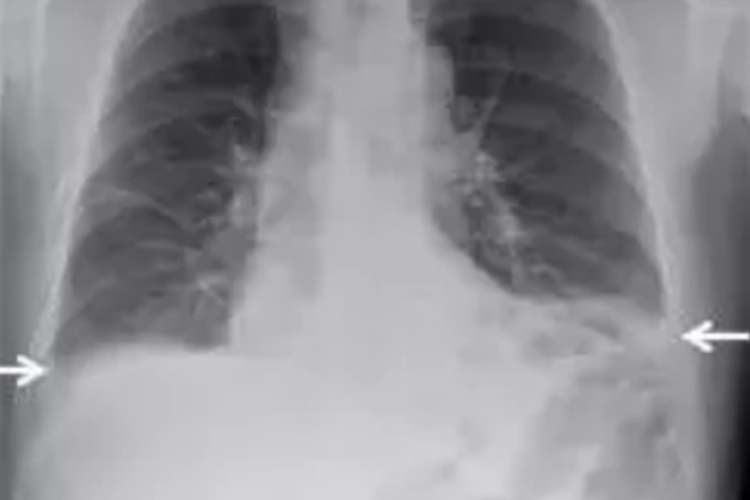

胸膜炎还可出现胸腔积液,大量胸腔积液压迫肺、心和纵隔时,可导致呼吸困难,且积液产生和聚集的越快、越多,呼吸困难就越明显,甚至可有端坐呼吸和发绀症状。感染性胸膜炎还可出现恶寒、发热的表现,炎症可引发刺激性咳嗽。

胸膜炎是胸膜的一种炎症,壁层胸膜分布着比较敏感的躯体感觉神经,当壁层胸膜受炎症刺激时,会引起明显的胸痛。如果不立即治疗,可致胸膜渗出,称为胸腔积液,大量胸腔积液会压迫肺、心和纵隔,导致呼吸困难。